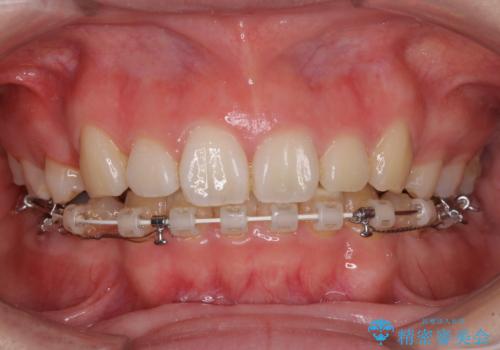

目立たない装置で出っ歯を治したい ハーフリンガル矯正

- ハーフリンガル

- 口元の突出感を気にして来院された患者様です。

上下左右の第一小臼歯4本を抜歯して口元を下げる治療計画としました。

目立たない装置が希望であったため、上顎が裏側装置である、ハーフリンガル装置を選択されました。